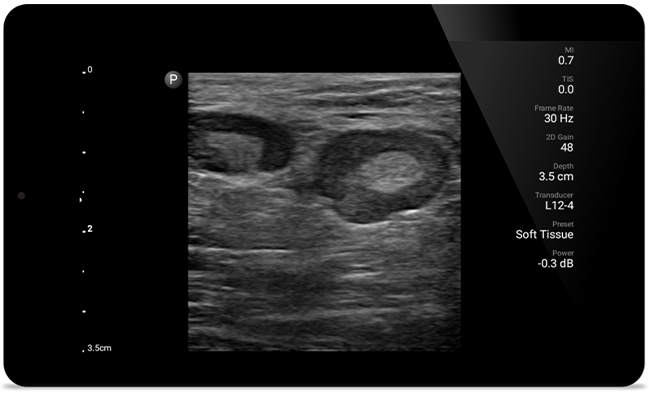

Beneficiaţi de claritatea ecografelor mai mari cu Lumify

SonoCT consolidează imagistica ţesutului real, eliminând în acelaşi timp artefactele aleatorii. Această tehnologie produce imagini superioare imagisticii convenţionale la până la 94% dintre pacienţi.